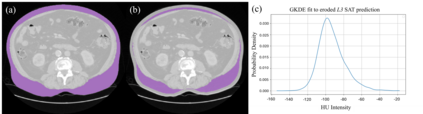

Purpose: The distribution of visceral adipose tissue (VAT) in cystectomy patients is indicative of the incidence of post-operative complications. Existing VAT segmentation methods for computed tomography (CT) employing intensity thresholding have limitations relating to inter-observer variability. Moreover, the difficulty in creating ground-truth masks limits the development of deep learning (DL) models for this task. This paper introduces a novel method for VAT prediction in pre-cystectomy CT, which is fully automated and does not require ground-truth VAT masks for training, overcoming aforementioned limitations. Methods: We introduce the Kernel density Enhanced VAT Segmentator ( KEVS), combining a DL semantic segmentation model, for multi-body feature prediction, with Gaussian kernel density estimation analysis of predicted subcutaneous adipose tissue to achieve accurate scan-specific predictions of VAT in the abdominal cavity. Uniquely for a DL pipeline, KEVS does not require ground-truth VAT masks. Results: We verify the ability of KEVS to accurately segment abdominal organs in unseen CT data and compare KEVS VAT segmentation predictions to existing state-of-the-art (SOTA) approaches in a dataset of 20 pre-cystectomy CT scans, collected from University College London Hospital (UCLH-Cyst), with expert ground-truth annotations. KEVS presents a 4.80% and 6.02% improvement in Dice Coefficient over the second best DL and thresholding-based VAT segmentation techniques respectively when evaluated on UCLH-Cyst. Conclusion: This research introduces KEVS; an automated, SOTA method for the prediction of VAT in pre-cystectomy CT which eliminates inter-observer variability and is trained entirely on open-source CT datasets which do not contain ground-truth VAT masks.